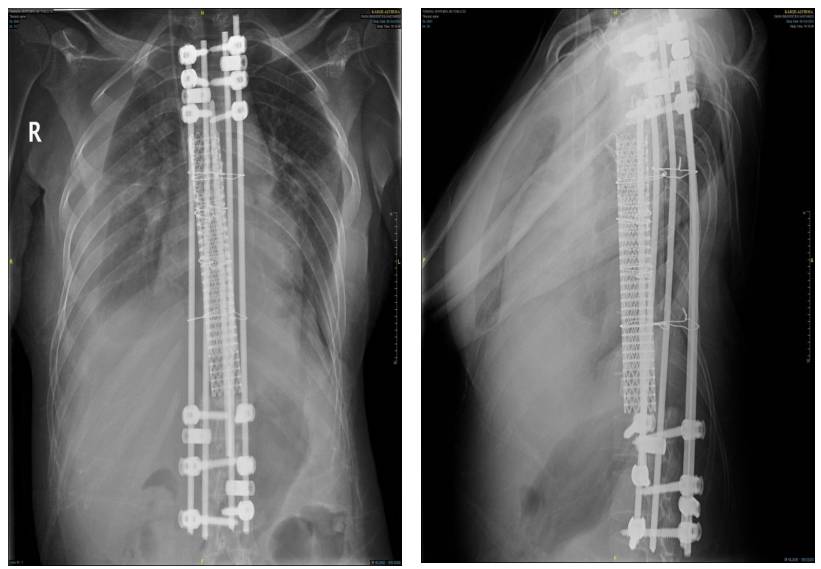

Ameliyat sonrası: Röntgende korpektomi sonrası fibula, cage ve enstrümentasyon uygulaması görülmekte